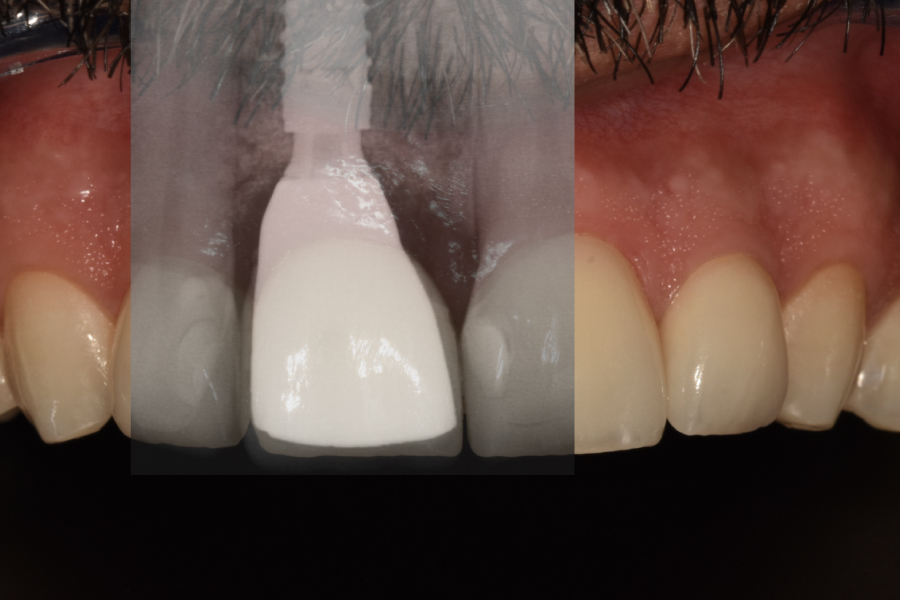

Fase 2: Controles y Segunda Etapa (Mes 4)

- Confirmación de osteointegración (ISQ > 70).

- Impresión convencional para realizar un encerado diagnóstico estético y posteriormente una realización de réplica del perfil de emergencia con la técnica de Hinds, para solapar una medida convencional con una digital (escáner intraoral).

- Restauración definitiva:

Pilar de zirconio ceramizado implanto-soportado monolítico (translucidez media, color A1)

Carillas de disilicato de litio (IPS e.max Press, espesor 0.6mm) de 12 a 21, cementadas con resina dual